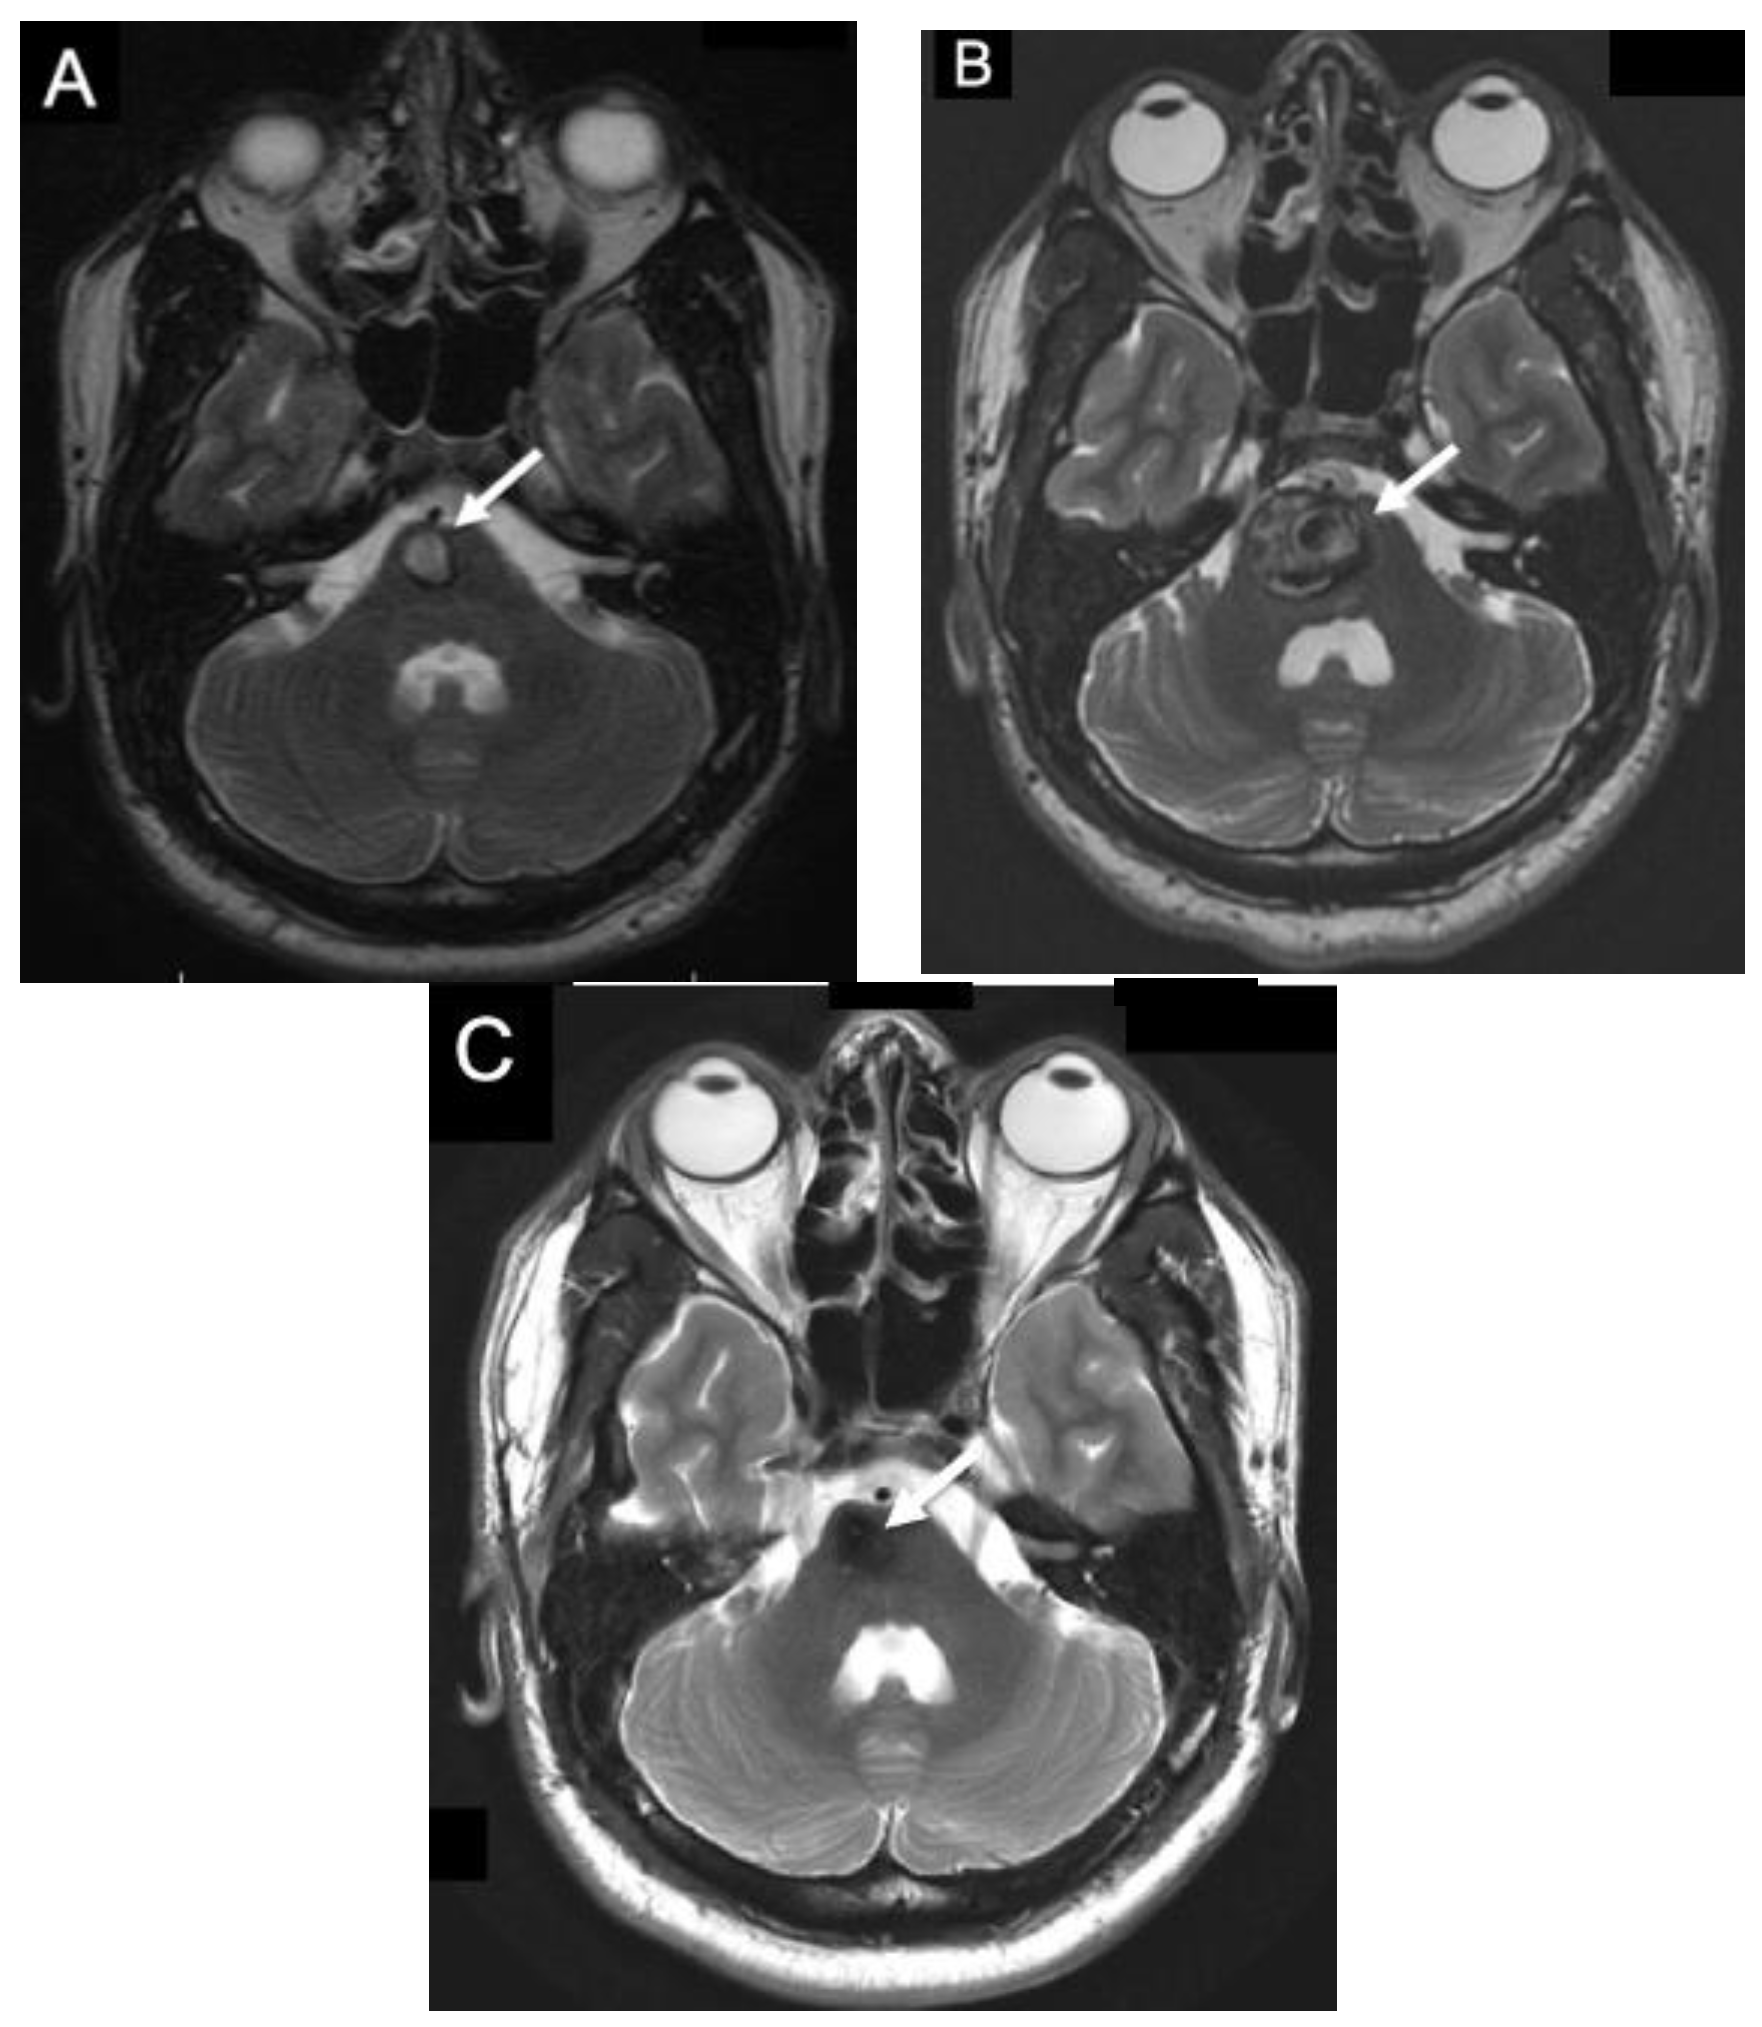

7. Management of Symptomatic Infratentorial Cavernomas